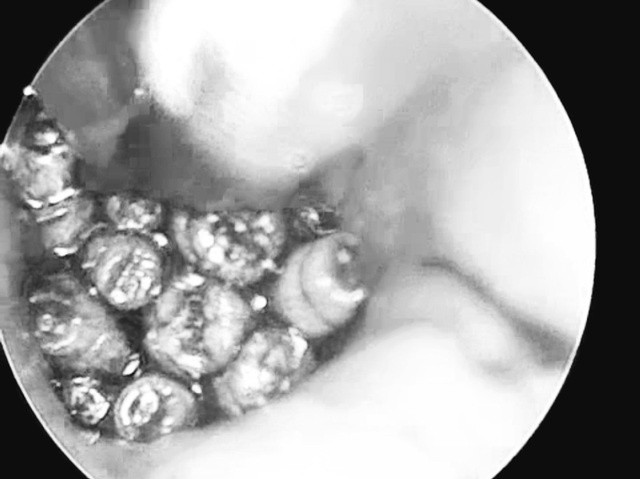

| Giòi sống trong tai bệnh nhân. Ảnh: Bệnh viện Đa khoa tỉnh Quảng Trị |

Thực hiện nội soi, các bác sĩ phát hiện ống tai hẹp, đọng nhiều máu tươi. Khi hút sạch máu, quan sát thấy dị vật màu trắng di động. Sau khi làm các xét nghiệm, các bác sĩ đã nội soi và gắp ra hàng chục con giòi lấp đầy hòm nhĩ, màng nhĩ thủng rộng. Hiện sức khỏe bệnh nhân ổn định và tiếp tục được theo dõi tại bệnh viện.

BS.CKII Đinh Viết Thanh-Trưởng khoa Tai Mũi Họng cho biết, đây là trường hợp rất hiếm gặp ở bệnh nhân tiền sử bị viêm tai giữa, có mủ sẽ thu hút ruồi cái đến đẻ trứng và phát triển thành giòi sau vài giờ, càng để lâu càng nguy hiểm.

Khi chúng lớn lên có thể tấn công tai giữa tai trong và các cơ quan xung quanh, gây biến chứng nghiêm trọng như viêm màng não, viêm tai trong rồi dẫn đến tử vong.